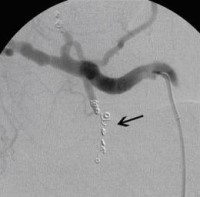

Postoperative abdominelle Blutungen bei chronischer Pankreatitis vor Embolisation der Art. gastroduodenalis mittels Metallspiralen (Coils)

(Bild 2 von 5)